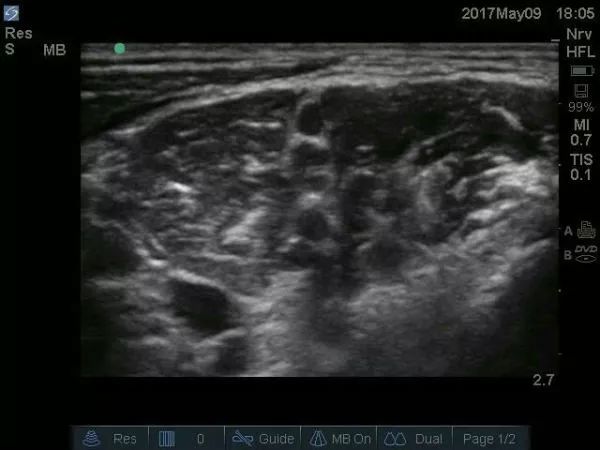

超声下肌间沟水平臂丛的走行图像,上面是胸锁乳突肌,左右是前、中斜角肌。肌间沟水平下可清楚看到呈串珠样的臂丛,C5、C6、C7等。请大家注意下,有的时候能看见5个“串珠”,不要以为是臂丛的5个根即C5、C6、C7、C8、T1,肌间沟往往是在颈椎7水平,怎么可能看到C8、T1,其实就是C5、C6、C7,那为什么是5个“串珠”?因为C6及C7在肌间沟水平已经分出2根,要避免在这2根汇合处之间穿刺而造成C6及C7的神经损伤。